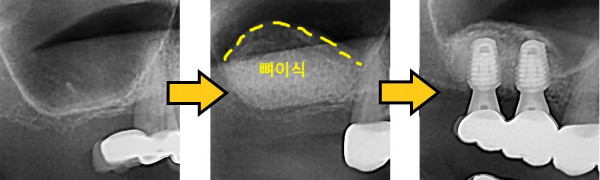

임플란트 뼈이식 + 임플란트

826e40416d712e6cd444a78bde93df4b_1767867938_0135.jpg